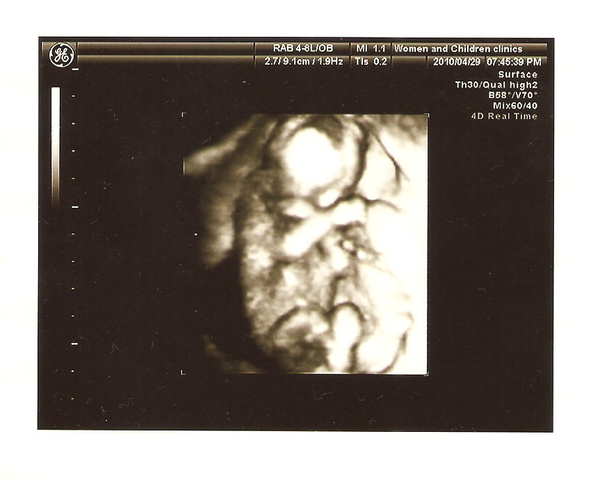

醫生仔細的看超音波,跟我說嘴巴正常 (我當然看不出來有沒有正常)

婦兒安螢幕比較大而且超音波清晰很多,加上醫生解說非常詳細又有耐心,我真的考慮要跳槽了...